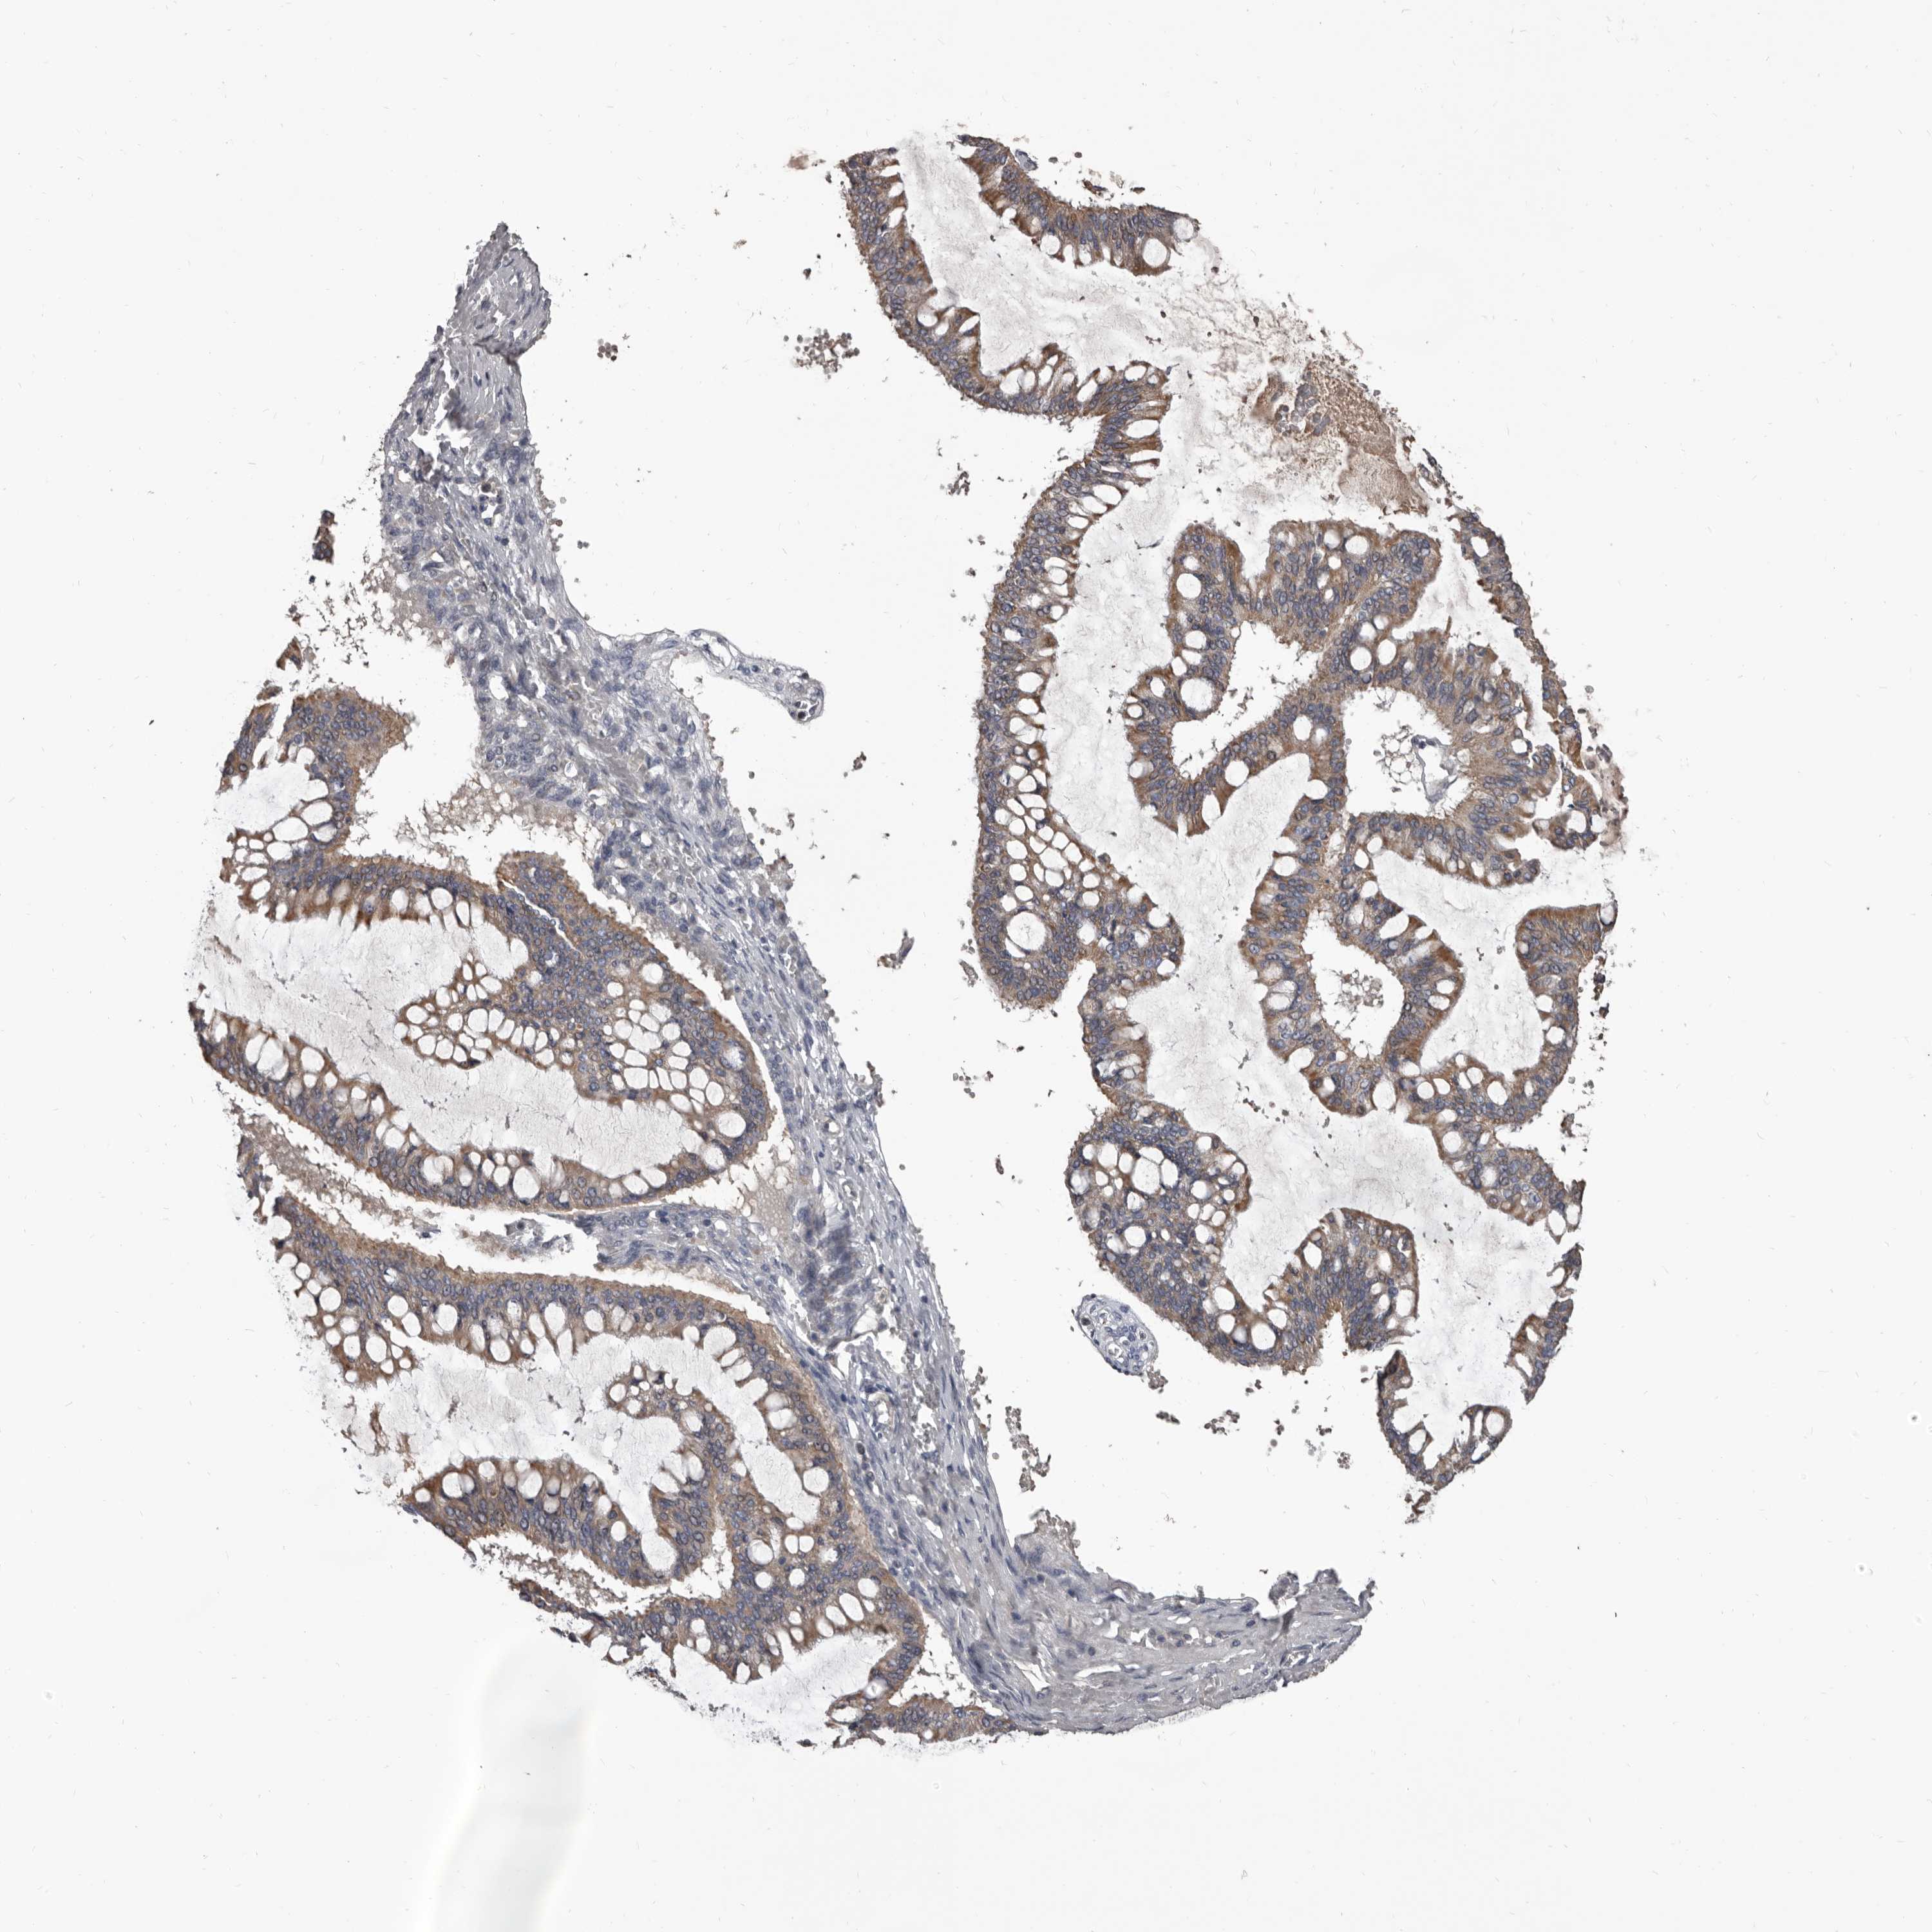

OVARIAN CANCER - Protein expressioni

A mouse-over function shows sample information and annotation data. Click on an image to view it in a full screen mode. Samples can be filtered based on level of antibody staining by selecting one or several of the following categories: high, medium, low and not detected. The assay and annotation is described here.

Note that samples used for immunohistochemistry by the Human Protein Atlas do not correspond to samples in the TCGA dataset.

Antibody stainingi

Antibody staining in the annotated cell types in the current human tissue is reported as not detected, low, medium, or high, based on conventional immunohistochemistry profiling in selected tissues. This score is based on the combination of the staining intensity and fraction of stained cells.

Each image is clickable and will lead to virtual microscopy that enables deeper exploration of all samples and also displays staining intensity scores, fraction scores and subcellular localization as well as patient and tissue information for each sample.

Antibody HPA029715

Antibody HPA029716

Cystadenocarcinoma, serous, NOS

Carcinoma, endometroid

Cystadenocarcinoma, mucinous, NOS

Carcinoma, NOS